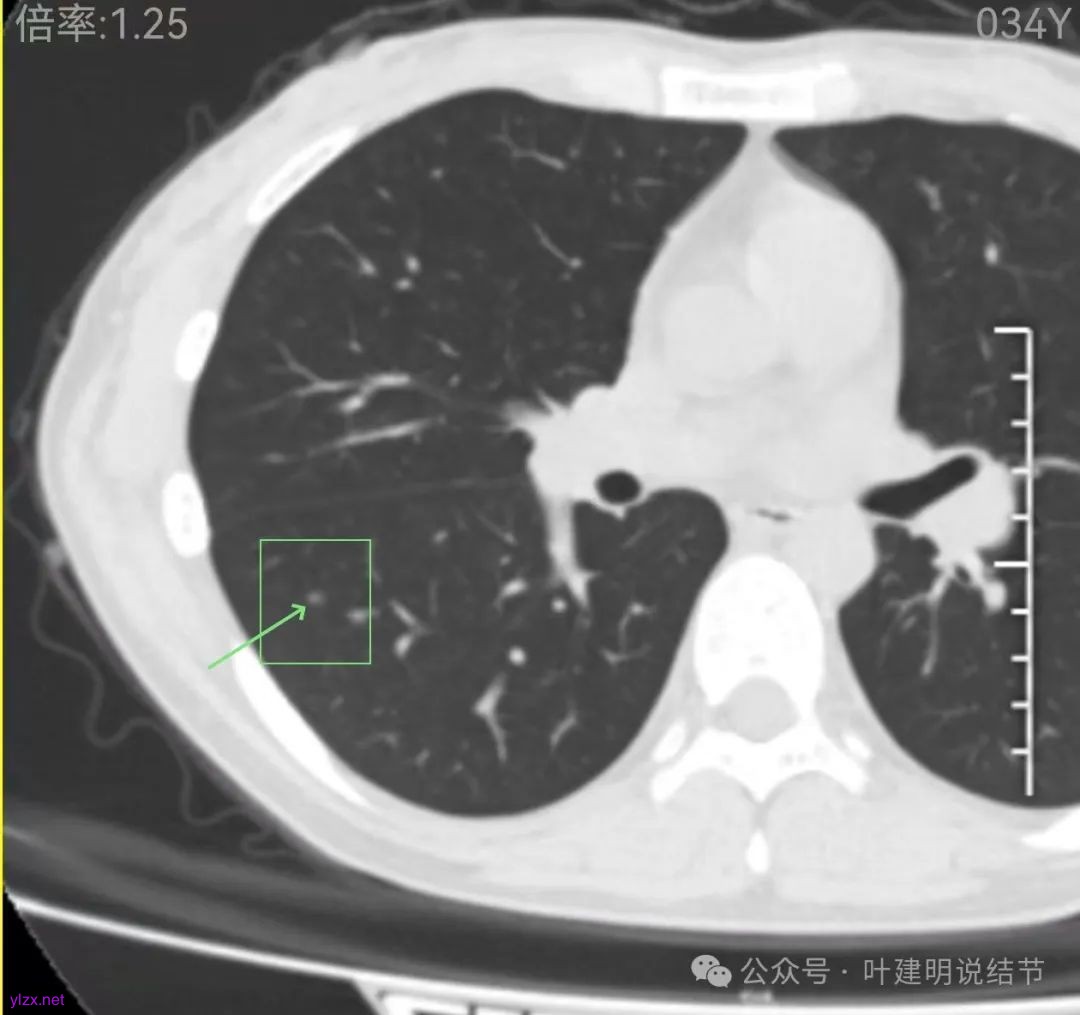

先来看2024年12月的影像:

左上叶淡而轮廓欠清楚的磨玻璃结节,缺乏聚拢性,没有收缩力。

在上叶淡而轮廓较清,密度不太纯略显杂乱的小磨玻璃结节。

右下叶磨玻璃结节伴空泡征,轮廓较清,瘤肺边界清楚。